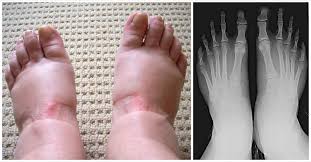

Vondt I Foten Arsaker Diagnose Behandling

Vondt I Foten Arsaker Diagnose Behandling from www.vondt.net